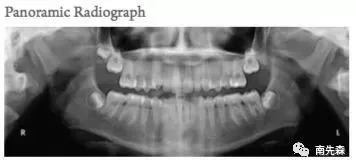

正常情况下,要出治疗方案的所需的必要资料,除了正面照、侧面照、45°侧面照这些基础的:

还有头颅侧位照,以便于头影测量分析,研究面部硬软组织容貌相关解剖标志点的角度关系等。